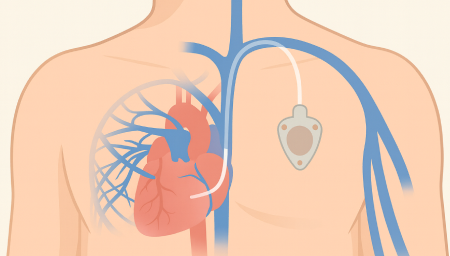

Chemoport는 항암제처럼 자극이 강한 약물을 안전하고 안정적으로 투여하기 위해 흉부 피부 아래에 이식하는 중심정맥 사용 포트입니다. 팔 혈관이 약하거나 반복 주사로 인한 통증이 걱정되는 환자에게 도움을 줄 수 있으며, 장기간 치료가 필요한 경우 편안하게 항암 치료를 지속할 수 있도록 설계되어 있습니다.

항암관(Chemoport)삽입 과정

01

국소마취 후 작은 절개를 시행 (보통 쇄골 아래 약 2~3cm 정도 절개)

02

정맥에 카테터 삽입 후 포트와 연결

03

방사선으로 카테터 위치 확인

04

피부 봉합 후 소독 드레싱